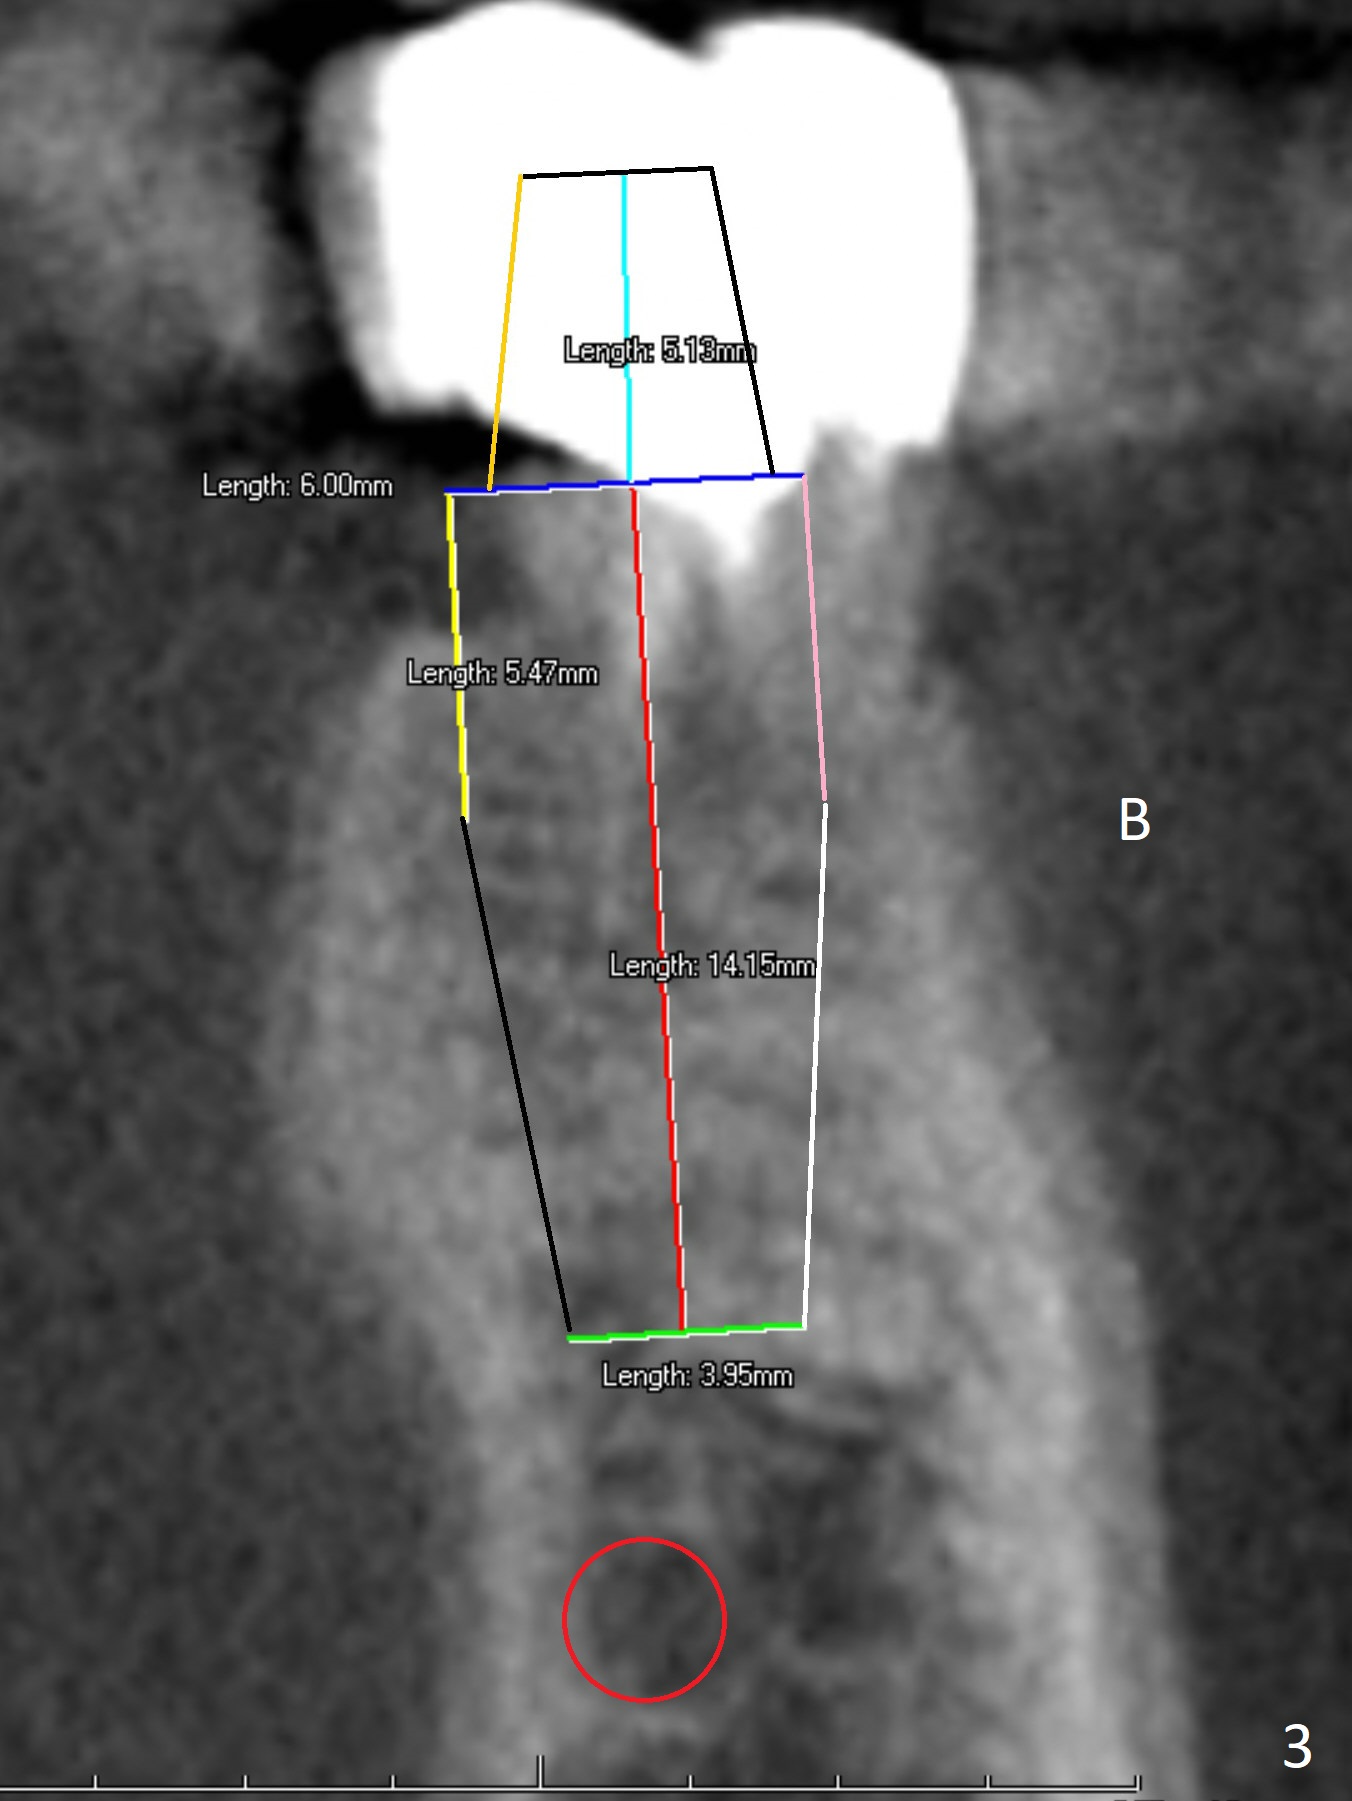

A 64-year-old man will return for #19 extraction and implant. Use IS drills with 10 mm stoppers until 4.5 mm, followed by 5x17 mm tissue-level tap (14 mm gingival level) and PA. Make sure that tap and later implant threads are in the bone or can at least be covered by bone graft (Fig.2,3).